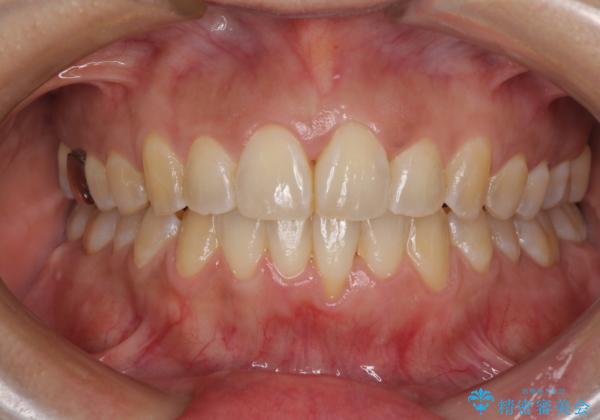

インビザラインによる狭窄歯列の拡大矯正

- 前歯のデコボコを治したいとのことで来院された患者様です。

上下顎ともに歯列全体の後方移動と側方拡大、IPR(歯と歯の間を削る)によってデコボコが解消するように設計し、インビザラインにより治療を行うこととしました。

治療途中で関西に転勤となってしまったため、東京に出張で来るタイミングに合わせて治療を進めることになりました。そのため、治療期間が長くなってしまいましたが、無事に仕上げることができました。